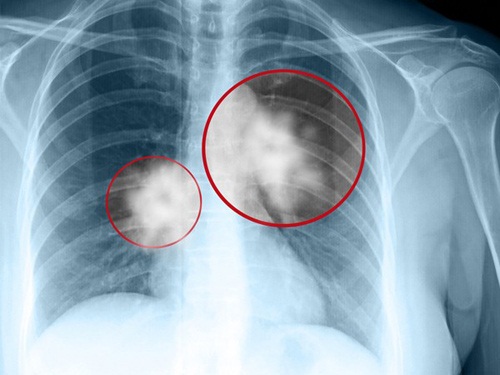

Bệnh ung thư phổi vô cùng nguy hiểm, có đến 70% người mắc bệnh ung thư phổi tử vong chỉ trong vòng 1 năm sau khi phát hiện.

Vậy, căn bệnh ung thư phổi nguy hiểm và có sức tàn phá như thế nào đối với cơ thể con người. Theo các chuyên gia về ung thư, ung thư phổi là một trong số những căn bệnh có tỷ lệ mắc nhiều nhất hiện nay đặc biệt là ở nam giới, độ tuổi mắc bệnh ung thư phổi nhiều nhất là từ 45-70 tuổi, tuy nhiên xu thế hiện nay đang ngày càng trẻ hóa.

Điều đáng nói, căn bệnh ung thư này có tỷ lệ người mắc tử vong ngay trong năm đầu tiên phát hiện bệnh có tỷ lệ rất cao chiếm khoảng 70%, thậm chí có trường hợp từ khi mắc bệnh và tử vong chỉ trong vòng chưa đầy 6 tháng.

BS Phương cho rằng, ung thư phổi được chia làm hai loại, ung thư phổi không tế bào nhỏ và ung thư phổi tế bào nhỏ. Đối với ung thư phổi tế bào nhỏ, bệnh tiến triển rất nhanh, di căn sớm, tái phát nhanh, nhạy cảm với hóa chất.

Còn đối với ung thư phổi không tế bào nhỏ, bệnh tiến triển chậm hơn, đáp ứng được với hóa chất, loại ung thư này chiếm tỷ lệ khoảng 85 đến 87% tổng số ca.

Có đến 70% người mắc ung thư phổi tử vong trong 1 năm đầu phát hiện.